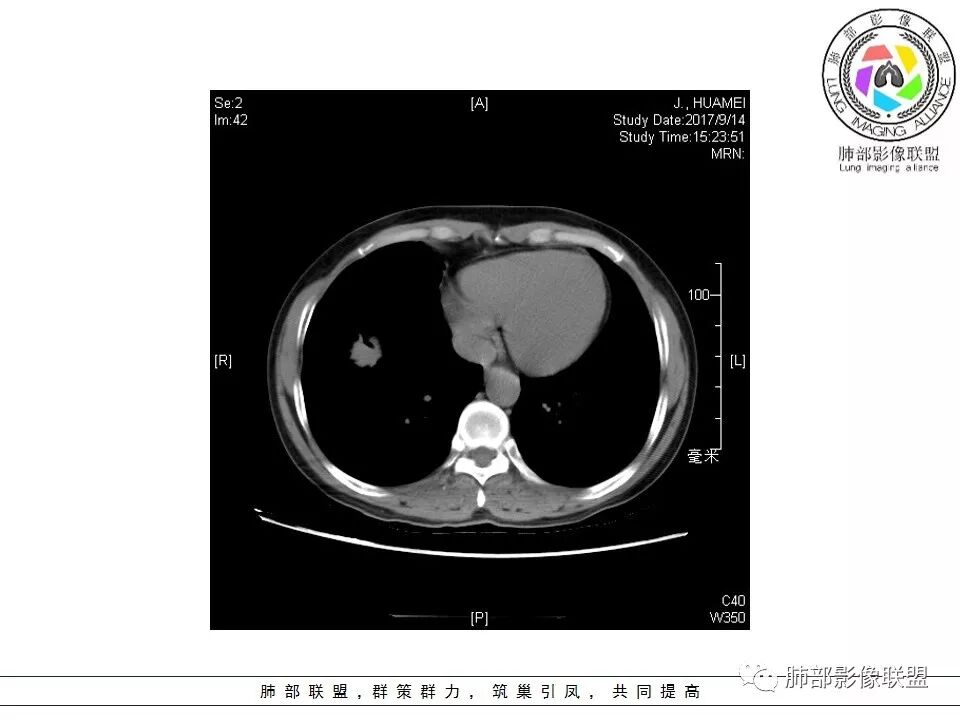

患者中年女性,因“体检发现右下肺占位4天。”入院,肿瘤标记物NSE轻高。

胸CT:右肺下叶前基底段占位性病变,内可见支气管穿过,病灶边缘不规则,呈浅分叶,未见明显毛刺。纵隔窗可见病灶密度相对均匀,增强可见病灶强化,内可见血管增粗,边缘模糊,总体考虑恶性,腺?。良性疾病鉴别错构。

南边老师分析

这个病灶边缘还是有一点点恶性征象,有分叶,似乎有点地方还有一些小毛刺样感觉

部分区域整体以膨隆为主,部分区域稍收缩

内部支气管走形非常自然,达远端稍扩张;内部血管穿行也非常自然

内部密度比较均匀,我们一般来说,首先良性肿瘤不支持,因为它里面的血管走形太自然了;然后就是炎性病变跟恶性肿瘤,但是它的边缘膨隆比较厉害,有些地方还毛刺,不是很清楚,倾向一个恶性病变

恶性的血管穿行自然,包括支气管稍扩张,最常见还是淋巴瘤,它强化比较均匀;

粘液腺癌一般支气管扩张比较罕见,这个密度及强化太均匀,不是很符合,所以把淋巴瘤放前面,癌待排;

方向定在恶性的,炎性病变不是很符合